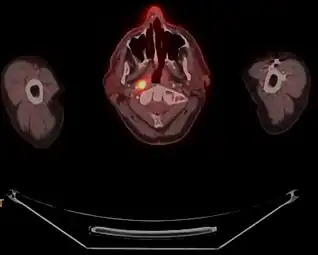

-

a) Axial PET/CT image reveals a FDG-avid mass in the nasopharynx in keeping with a known nasopharyngeal carcinoma b)axial CECT image shows the infiltrative nasopharyngeal carcinoma c) axial T2W MR image demonstrates the infiltrative nasopharyngeal carcinoma -